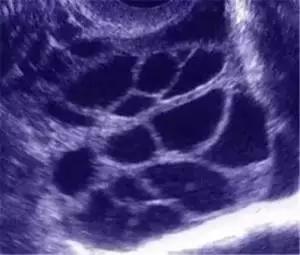

年轻(<30岁),身材瘦小(BMI<17)、 PCOS/PCOM患者、既往有OHSS史者,这类人群卵巢对促排卵药物的反应敏感,“试管婴儿”的成功率很高,但同时也是OHSS的高危人群。抗苗勒氏管激素(AMH)及基础窦卵泡数(AFC)是预测OHSS更客观直接指标。与年龄及BMI相比,AMH预测效果更好,当AMH>3.36ng/mL时,OHSS发生的风险增高。

同时促排卵时大剂量外源性促性腺素药物的应用,如果 HCG日血雌二醇(E2)> 15000 pmol/L、B超提示直径≧12mm的卵泡数超过20枚,那发生OHSS的几率是非常高的。

预防为先:在促排过程中,当B超发现OHSS倾向和盆腔积液征象时,可嘱咐患者避免剧烈运动以防止卵巢扭转,严重者需要补液扩容,预防和控制血管内水分外渗,血液浓缩发生。